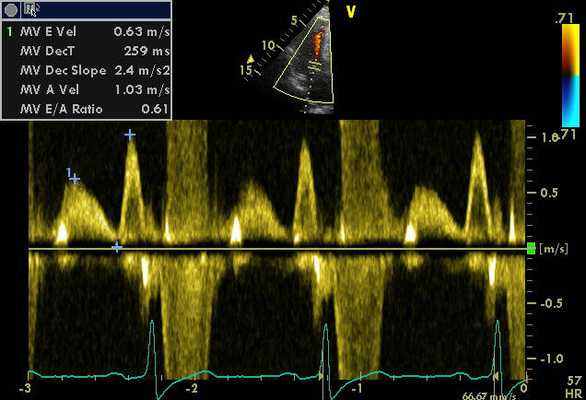

- Основные допплерографические характеристики трансмитрального и транстрикуспидального диастолического потока

- Е - раннее диастолическое наполнение (Vmax = 70-100 см\с)

- А - позднее диастолическое наполнение (в момент систолы предсердий, Vmax = 40-70 см\сек)

- Е\А = 1,0-1,5